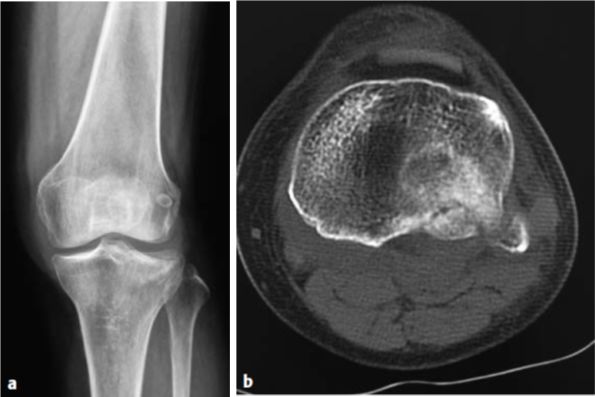

图6.8.1-22 a-c 使用骨替代物

a  一例65岁女性的41B3型骨折;b  CT矢状切面显示关节面塌陷;c  关节面复位后,使用骨替代物来填充骨缺损区域,采用锁定头螺钉和外侧支撑钢板来进行牢靠固定。